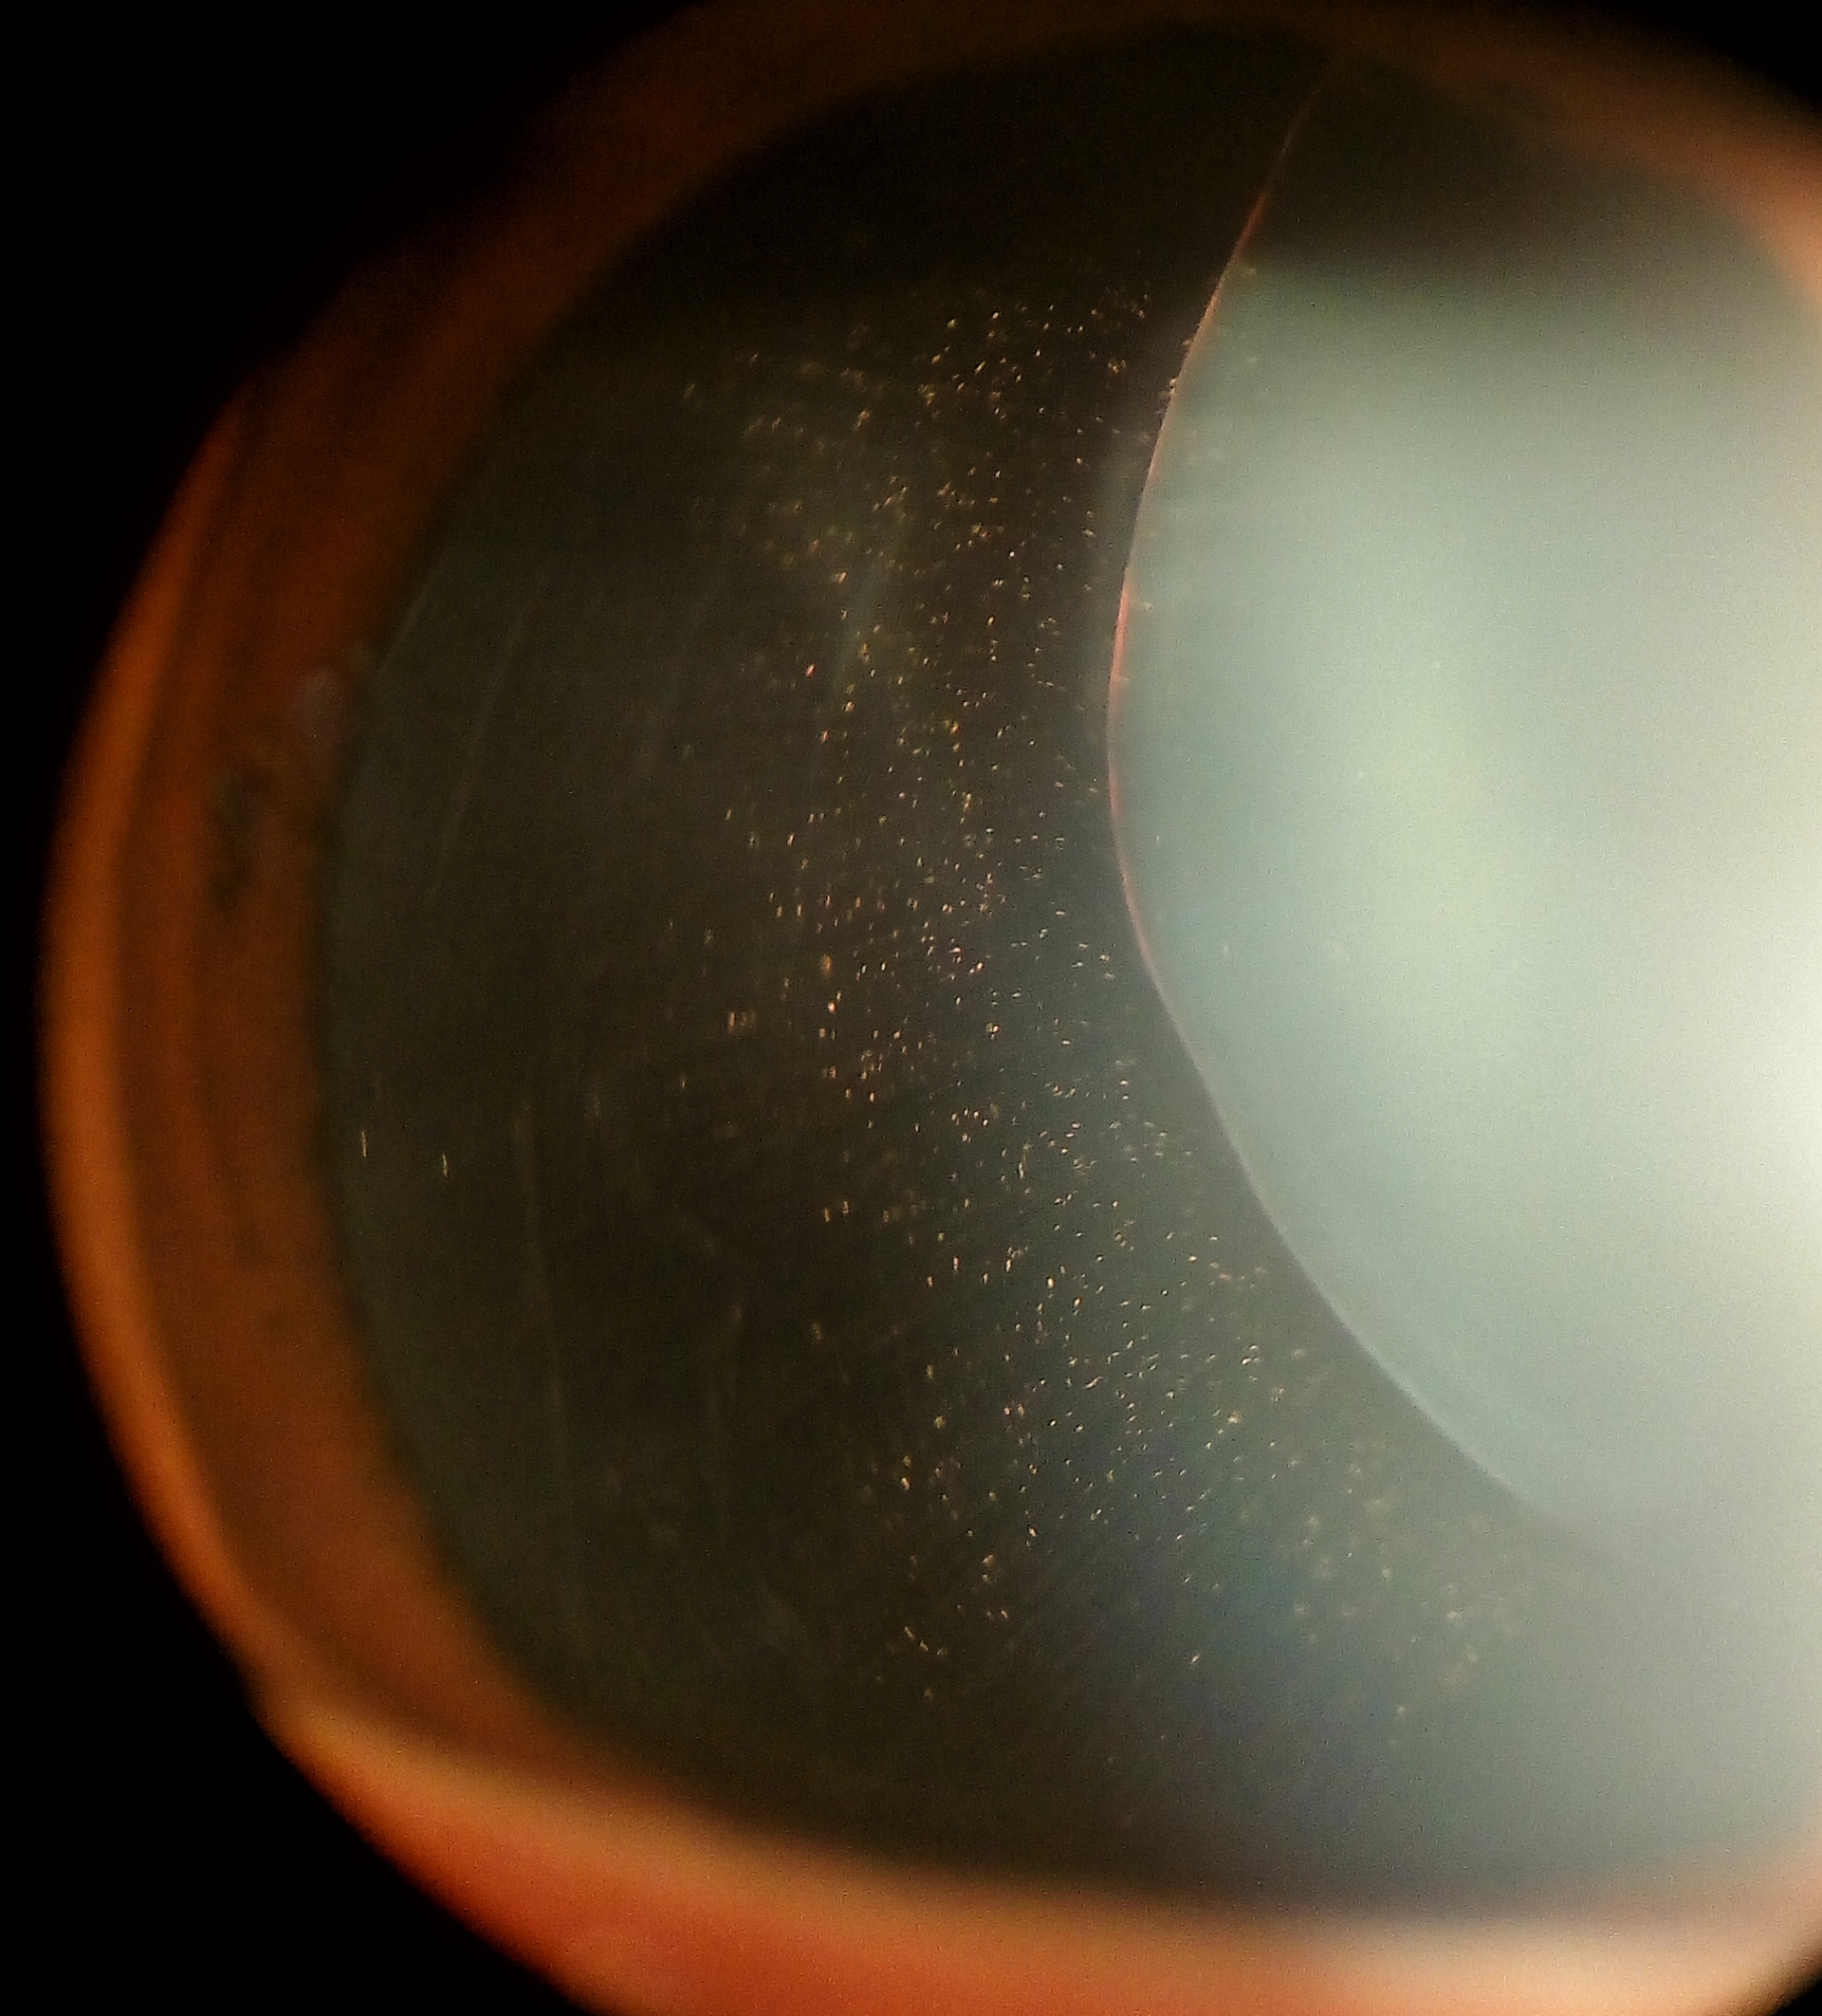

안과적인 특징은 공모양소수정체(spherophakia)입니다.

즉, 수정체가 찐빵과 같은 모양으로 넙데데하게 생깃것이아니라,

공모양으로 둥굴게 생겼습니다.

즉, 수정체 지름은 감소되어있고, 두께는 증가되어 있어

동공을 산동시켜보면 수정체의 전체 모양이 완전히 관찰가능합니다.